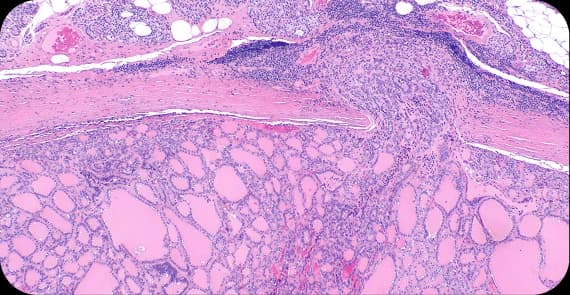

There are several types of thyroid cancer, each with distinct characteristics.

The most common type of thyroid cancer, it is typically slow-growing and often highly treatable.

Typically, it spreads through the bloodstream instead of lymph nodes.

Arises from specialised C cells that produce calcitonin.

This type is a comparatively rare and aggressive form.